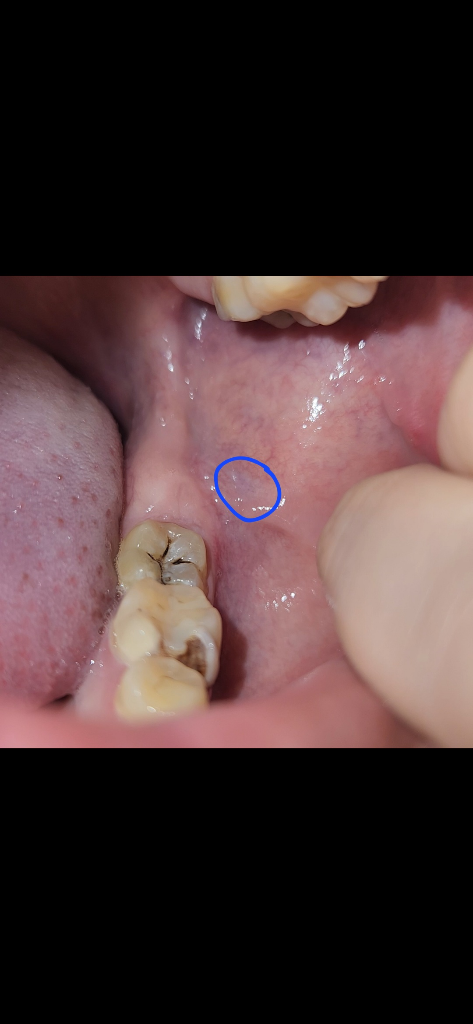

볼살이 치아에 씹히면서 생기는 현상입니다. 크게 문제가 잇는건 아니니 걱정하지 않으셔도 됩니다.

사진으로는 정확하게 확인 하기 힘드나 때로 불편감이 없다면 큰 문제가 없을 가능성이 높습니다.

자세한 확인을 위해서 치과에서 진료를 받아 보세요.